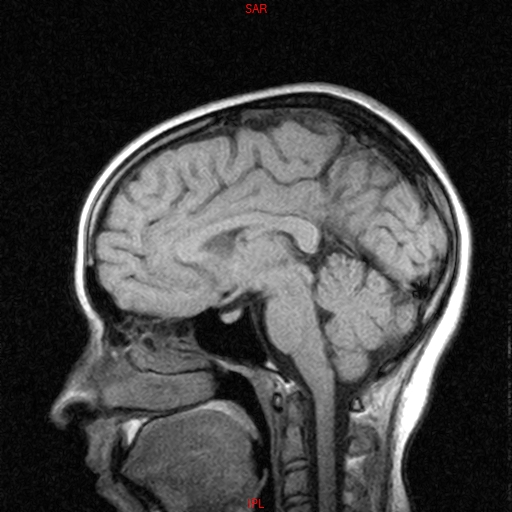

• RESONANCIA NORMAL CRANEAL T1 SAGITAL